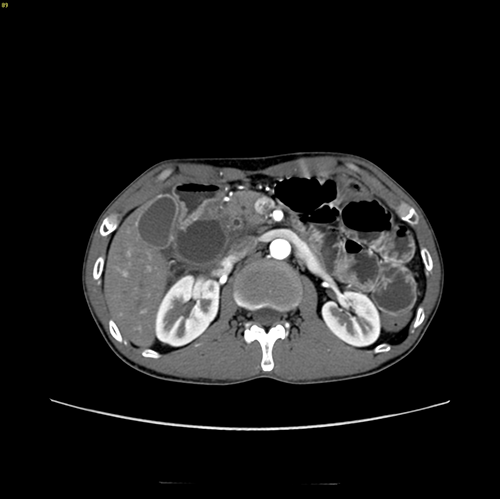

慢性胰腺炎伴假性囊肿形成